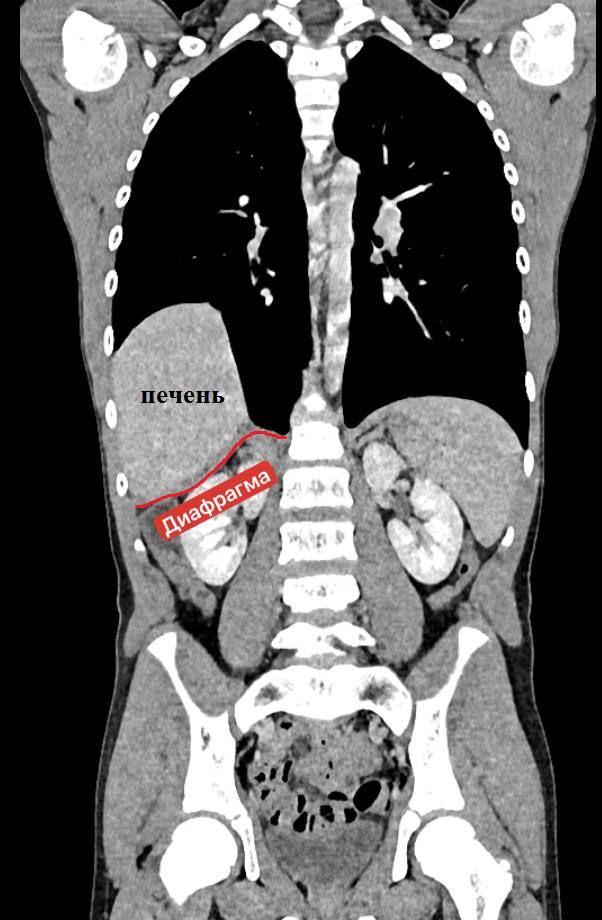

Диафрагмальную грыжу у мальчика обнаружили случайно, когда у ребенка развилась пневмония, и рентгеновское обследование выявило аномалию. Это редкий случай: как правило, такие грыжи диагностируются в младенческом возрасте, но в данном случае патология оставалась незамеченной целых 13 лет.

Подростка успешно и своевременно прооперировали. Это позволило избежать серьезных осложнений. Сейчас юный пациент чувствует себя хорошо, его выписали на амбулаторное лечение.